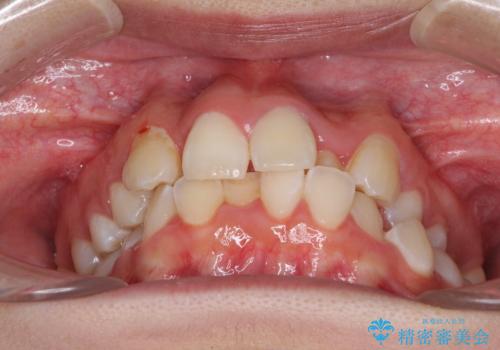

- 骨格的な咬み合わせのズレ、前歯のデコボコとクロスバイトを気にして来院された患者様です。

口元の突出感が若干あり口が閉じにくく、デコボコが強いため、上下左右の小臼歯計4歯を抜歯し、ワイヤー装置による矯正治療を行うこととしました。